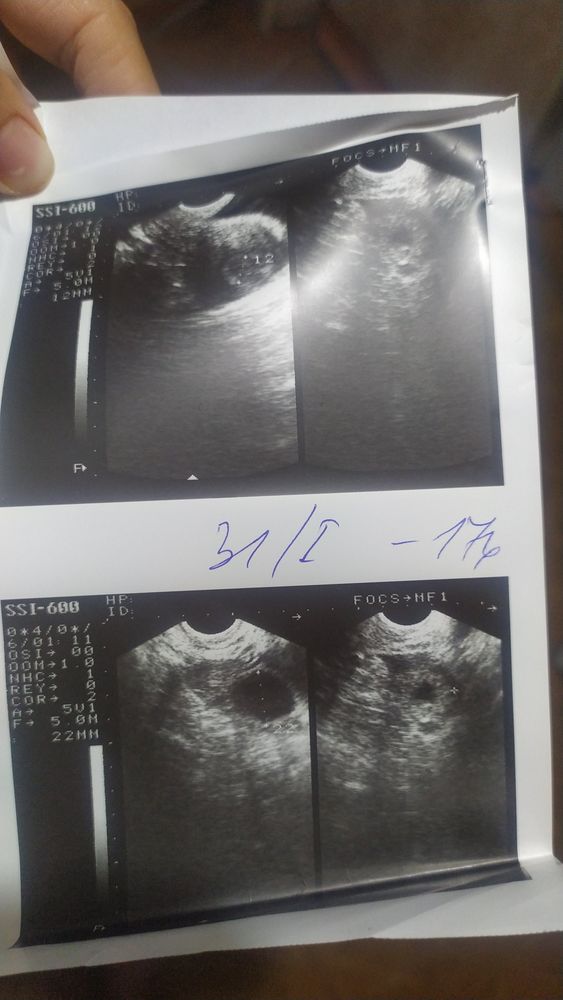

Всем привет. 5 августа было прерывание беременности ЗБ, чистка под наркозом. Сделали первое УЗИ и обнаружили повреждённые эндометрии. Вопрос у кого была схожая ситуация, что после чистки повреждённые эндометрии? долго восстанавливались и как? УЗИ прекреплю может кто поможет разобраться.

Врач говорит что если повреждённые эндометрии вдальнейщем могут плохо питать плаценту. Дело втором, что хочу как можно быстрее преступить к планированию беременности

На какой день цикла после М сделано узи? Сколько мм по заключению? На фото видать пробелы в эндометрии, но фото у вас не четкие. Я очень долго восстанавливала свой эндометрий после скаблежки((

Нина, чистка механическая была. При чистки повредили слой в матке. эндометрии теперь не равномерно расположены и появились места где эндометрии сильно поврежденны. Извиняюсь что не могу точно сказать как это называется

Что на картинках УЗИ вообще не понятно, яичники наверное.

Нина, есть разные слои эндометрия, если поврежден функциональный, то он может больше не нарастать в этих местах.

От сюда и такие "пробелы" на узи.